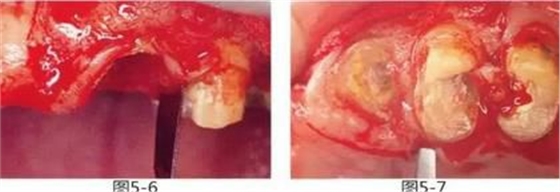

圖5-6,7

使用手術(shù)刀、7號(hào)牙齦刀、11號(hào)牙齦刀、咬骨鉗,盡可能將牙根周圍的軟組織進(jìn)行整體切除。

圖5-8,9

使用金剛砂車針削除牙根周圍的牙槽骨,從牙槽嵴頂露出至少3mm的健全牙體組織。